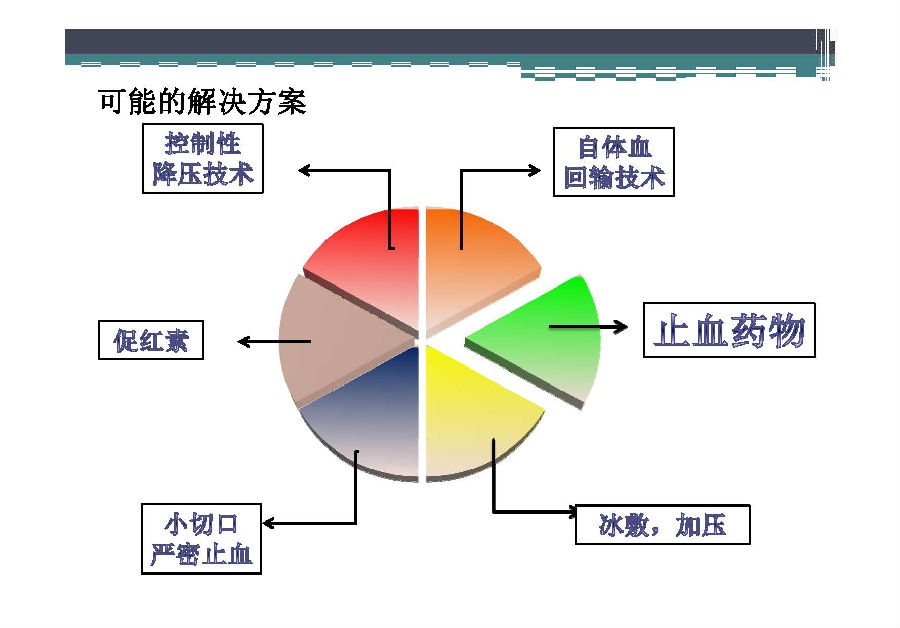

对于关节外科而言快速康复实际上是以病人加速舒适康复为目的,加强围术期的综合管理,包括疼痛和睡眠管理、血栓预防管理、感染预防管理、围术期血液管理,减少放置引流管、尿管、减少止血带应用,减少术后恶心呕吐,尽早进食,尽早康复等,逐步达到无血、无痛、无栓、无感、无肿、无管、无吐、无带等优良效果。为此,小编特邀王坤正教授等多位关节外科的专家参与撰写快速康复外科在关节外科的应用的主题文章,共话“人工关节置换快速康复”新理念,探讨建立符合我国特色的关节置换围手术期管理与快速康复体系,促进我国关节外科技术整体发展与提高。